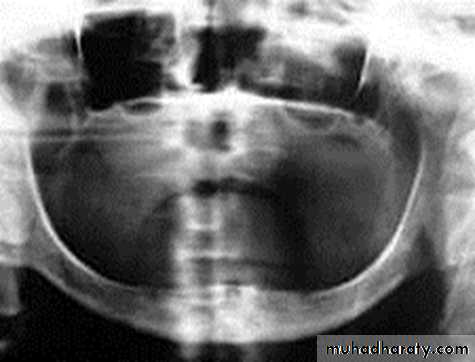

Epiosteal / Subperiosteal Implants

They placed directly beneath the periosteum overliying the bony cortex (not anchored inside the bone)Receive primary bone support by resting on it.

• Usually indicated in a severely resorbed, completely edentulous mandible which does not offer enough bone height to accommodate root form implants as anchoring devices.